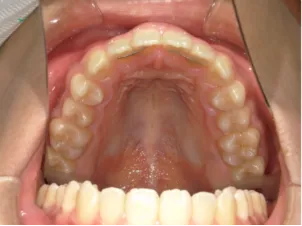

治療前①小5:スタート

| はじめのご相談 | 凸凹になりそうと一般歯科の先生に言われたのでみてほしい |

|---|---|

| カウンセリング・診断結果 | 下あごが後退しているタイプの出っ歯で、過蓋咬合で下あごが前に成長しにくいタイプの顔立ちです。 上の歯列弓が小さめで前歯に凸凹があります。 口元が閉じにくい口唇閉鎖不全があります。 *上記に対する治療の流れを説明し(拡大・前歯の並べ替え→出っ歯の改善→モノブロック装置(筋機能的咬合誘導装置)→必要によりマルチブラケット法)、以下の治療を提案しました。 |

| 行ったご提案・診断内容 | 成長期に行う治療と咬合治療をご提案しました。 成長期治療(成長時期にお口の環境を整え、適正な成長を促す治療)で、 ①歯列弓形態の修正、拡大と前歯を並べる。 ②出っ歯を治す専用の装置を使用する。 ③・MFT:舌や口唇などが正しい動きやポジショニングで機能し、鼻で呼吸できるようにする練習、毎日おうちで習慣づくように続けてもらいます。 ④拡大による顎顔面の適正な成長効果で口元を改善する(写真③)。 |